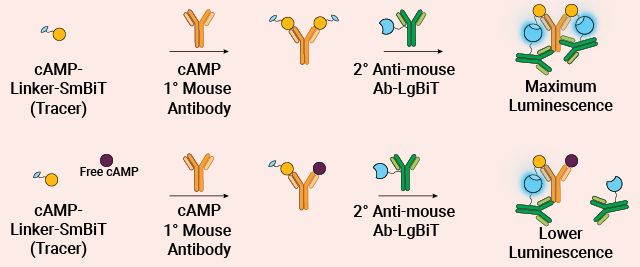

High-Throughput Screening of cAMP

Lumit® Technology offers a rapid, no-wash bioluminescent method for measuring cAMP. This homogeneous assay simplifies workflows, minimizes interference and delivers accurate, high-throughput results in minutes.